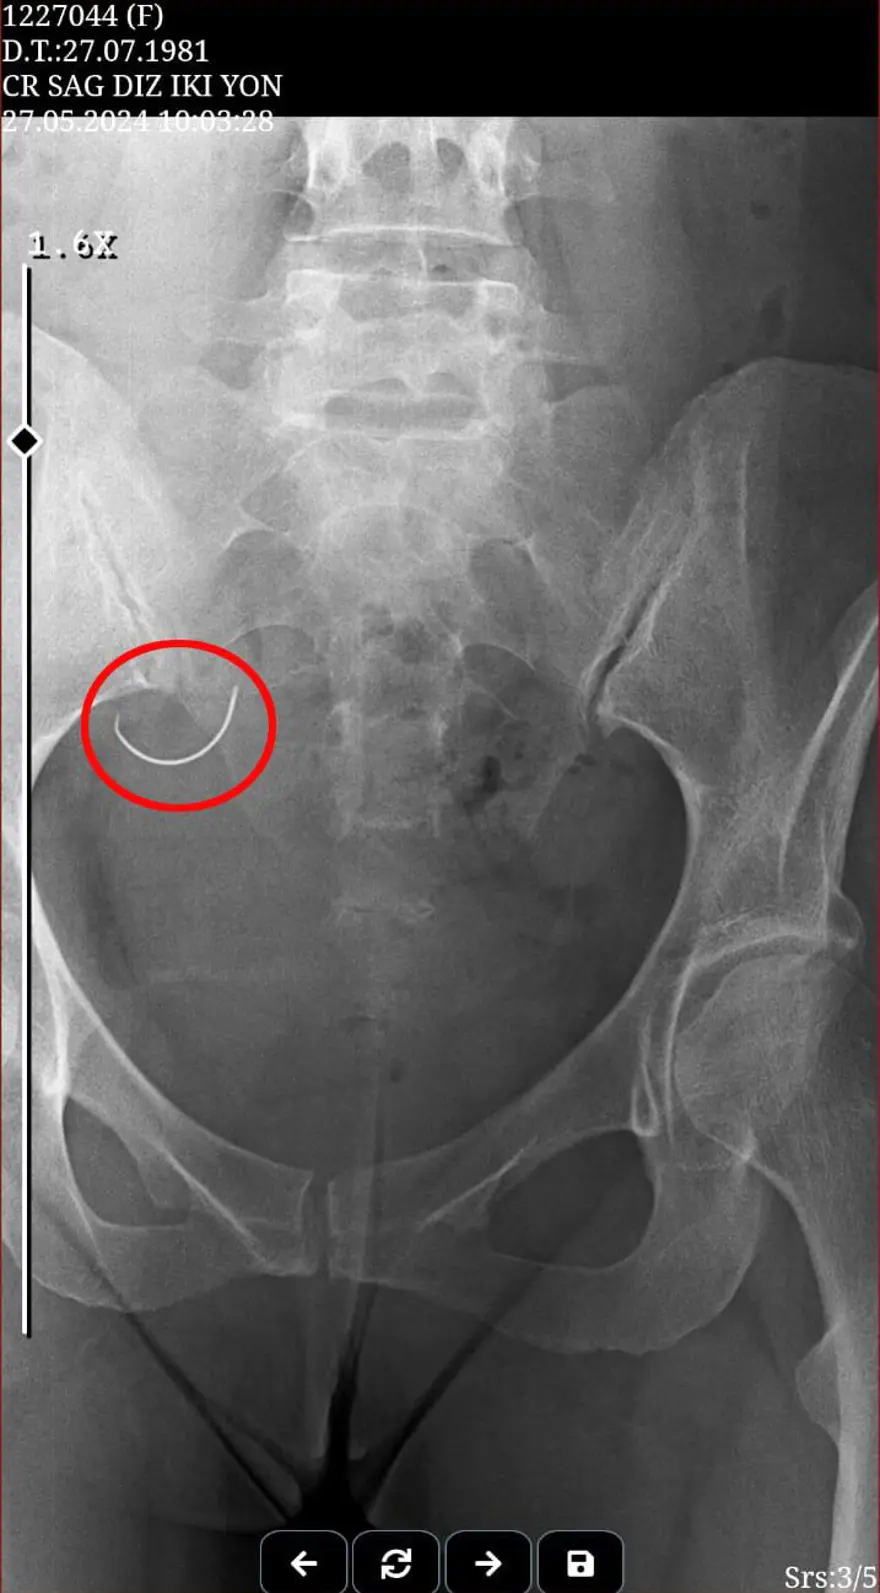

Ü.İ., iddiaya göre bebek sahibi olamadıkları gerekçesiyle suçladığı eşine, 26 Mayıs 2024 tarihinde fiziksel ve psikolojik şiddet uyguladı. Sabiha İ. olaydan 1 gün sonra adli muayene için gittiği Kumluca Devlet Hastanesi'nde, karnında ameliyat iğnesi unutulduğunu, röntgen filmi sayesinde öğrendi.

Sabiha İ., "Zorla evlendirildim, ilk evliliğimiz 1 yıl sürdü. Daha sonra boşanma davası açarak ayrıldım ama beni tehdit etmeye başladı. Mecbur bırakıldığım için tekrar evlendim. Evlendikten sonra çocuk istemeye başladı. Sağlık problemim vardı, doktorlar tüp bebek önerdi. Tüp bebek için miyom ameliyatı olmam gerekiyordu, ameliyat sonrası sıkıntılar yaşadım. Kocamla daha sonra aramız açıldı. İlk etapta doktorlar bir şey olmadığını söyledi ancak karnımda iğne unutulmuştu. Kocam doktorlara inandı, bana inanmadı." diye konuştu.